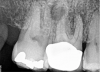

The new technology introduced in this article is based on advanced multisonic technology. Several current systems take advantage of ultrasonics and/or piezoelectric ultrasonic technology to deliver endodontic therapy. Some of these include MiniEndo (Kerr Dental), Varios® (NSK, nskdental.us), and Newtron® (Satelec, A-dec Inc, a-dec.com). The cases documented in this article feature the GentleWave® System (Sonendo®, sonendo.com), which employs a proprietary multisonic cleansing technology to deliver therapeutic irrigants into the root canal system, including lateral canals and tubules of complex root canal systems, while leaving the dentin largely intact.1,6-11 In the case shown in Figure 2 (preoperative radiograph) and Figure 3 (postoperative), the clinician was initially under the misconception that simple "cleaning and shaping" could be used for the root canal system in the conventional manner. The clinician evaluated the root canal system digitally in 2D and 3D before starting the case. The case was accessed, prepared, and cleaned and disinfected. Special attention to the digital imagery of the mesiobuccal root complex allowed the clinician to appreciate that the MB1 and MB2 merged before exiting from a common foramen. The 2D postoperative radiograph (Figure 3) illustrates that all of the mechanical objectives were realized.

Fig 2. Preoperative (Fig 2) and postoperative (Fig 3) radiographic images.

Figure 2

Fig 3. Preoperative (Fig 2) and postoperative (Fig 3) radiographic images.

Figure 3